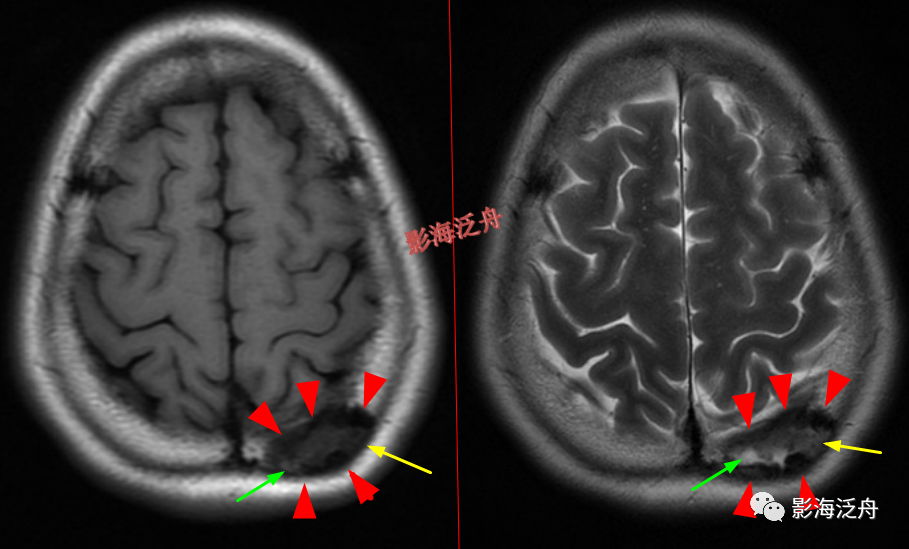

脑膜炎患者,桥前池内可见异常增多的血管影(红箭),正常人的桥前池因为脑脊液流动产生的伪影也可以看到池内絮状低信号(绿箭),但不如右侧患者的明显,这个观察起来比较困难,就如在腹部CT上观察患者是否存在肝脏肿大一样,需要一个经验积累的过程。黄箭指基底动脉,蓝箭指三叉神经。